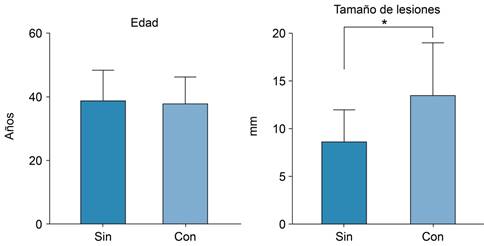

El promedio de edad de la población en estudio fue de 38.72 ± 9.12 años de edad, con una distribución normal o paramétrica según la prueba de Kolmogórov-Smirnov (p = 0.2). En cuanto a la localización de las lesiones observadas mediante el estudio de resonancia magnética, se encontró la distribución mostrada en la Tabla 1. El tamaño promedio de las lesiones encontradas fue de 9.76 ± 4.44 mm (Figura 6).

Figura 6: Promedio de edad y tamaño de las lesiones. El promedio de edad de la población en estudio fue de 38.72 ± 9.12 años de edad. El tamaño promedio de las lesiones encontradas fue de 9.76 ± 4.44 mm. * p ≤ 0.05.

Posteriormente, se realizó una separación de los casos en dos grupos: los que presentaron adenomiomas y los que no. Los datos observados se presentan en la Tabla 2. No se encontró correlación entre el tamaño de la lesión y su localización (p = 0.193).

| Edad (años)* | 38.92 ± 9.49 | 38.09 ± 8.16 | 0.7949 |

| Tamaño de la lesión (mm)* | 8.51 ± 3.33 | 13.4 ± 5.37 | < 0.001 |